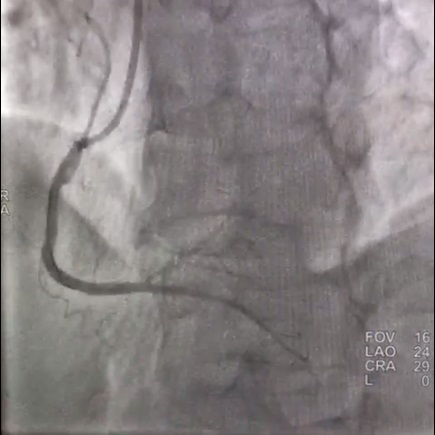

Сотрудники отделения рентгенохирургии в соответствии с самыми современными рекомендациями выполнили стентирование пораженных участков артерий и полностью устранили все сужения, имплантировав 3 стента с лекарственным покрытием.

Результаты стентирования